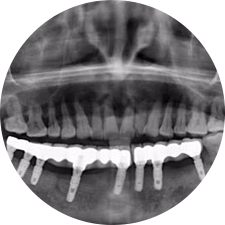

口腔種植是將人工牙根通過手術(shù)植入牙骨內(nèi),獲得牙槽骨牢固的支持,通過特殊的裝置和方式連接牙修復(fù)體,獲得與天然牙功能、結(jié)構(gòu)以及美觀相似的效果。

河北惟德口腔醫(yī)院擁有國內(nèi)豐富的半口/全口、即刻負(fù)重種植案例,十八年案例跟蹤分析,總結(jié)梳理出的各種不同類型的種植案例,Nobel種植體系針對半口/全口缺牙患者,通過4-8顆種植體可快速達(dá)到牙齒重建,不僅植入種植體較少,節(jié)省費(fèi)用,手術(shù)時間更短。

術(shù)前患者CBCT口掃1:1三維重建,模擬手術(shù)過程及預(yù)測術(shù)后治療效果,確定每顆植體植入的適合的種植位點(diǎn)、深度及角度,有效避免損傷頜骨重要解剖結(jié)構(gòu),提高手術(shù)準(zhǔn)確度與安全性。

Noble口腔種植體系基本不受年齡限制,適用于缺牙修復(fù),也適用于牙槽骨萎縮、骨質(zhì)疏松、高血壓、糖尿病、超高齡的患者,即種即用,只需少量微小種植體,便可輕松微痛快速重建全口咬合,特殊力學(xué)設(shè)計,針對許多年紀(jì)較大,骨質(zhì)條件差,身體耐受力差的缺牙老人也能完成“即種即用”,受到廣泛好評。

惟德口腔種植體系是以患者感受為中心,取代傳統(tǒng)種植牙手術(shù)需要翻瓣、打孔、縫合,術(shù)前、術(shù)中、術(shù)后的繁復(fù)流程,采用3D導(dǎo)航微創(chuàng)準(zhǔn)確種植技術(shù),通過數(shù)字化CAD/CAM掃描技術(shù)獲得缺牙患者口腔數(shù)據(jù),以數(shù)據(jù)為基礎(chǔ)重建口腔模型進(jìn)行模擬種植。